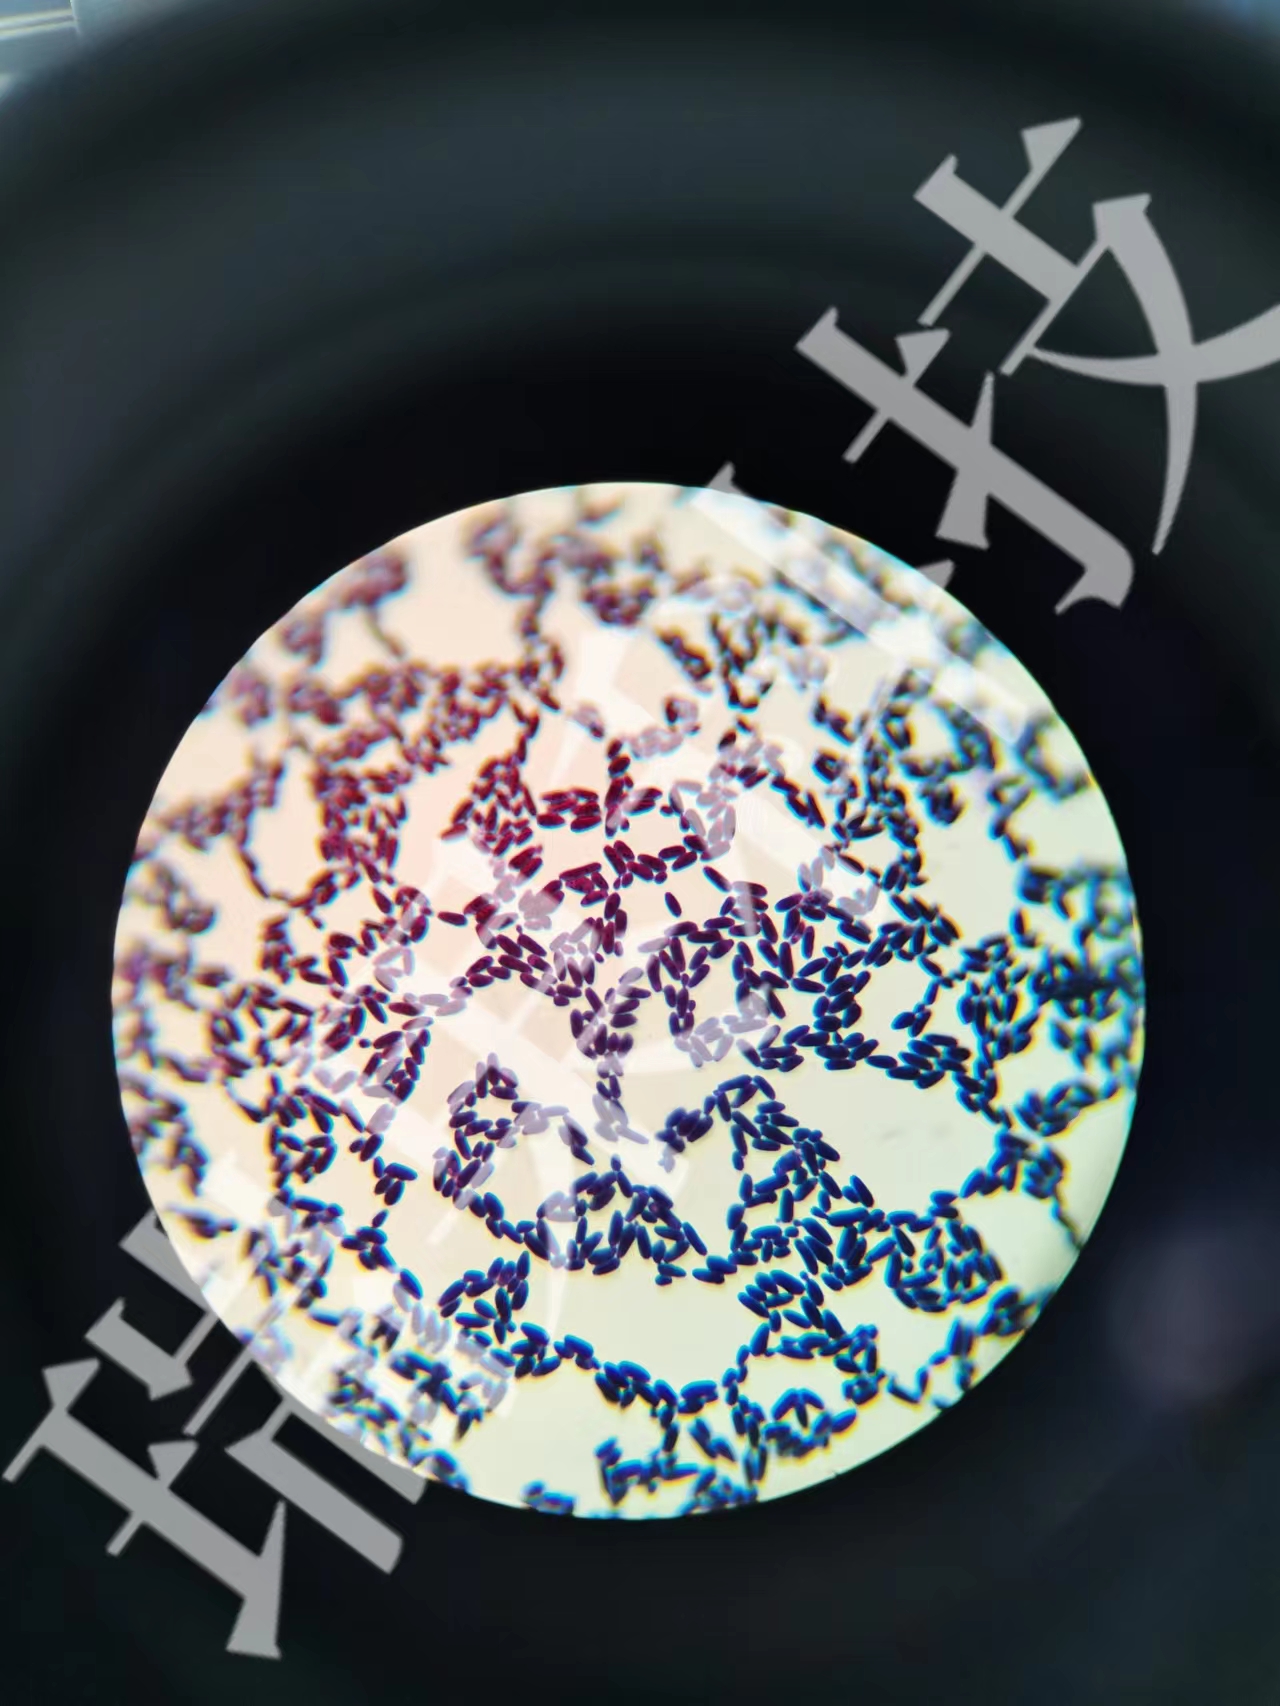

吉姆薩染色:染色原理和結(jié)果與瑞特染色法基本相同。但該法對(duì)細(xì)胞核和寄生蟲著色較好,結(jié)構(gòu)顯示更清晰,而胞質(zhì)和中性顆粒則著色較差。為兼顧二者之長(zhǎng),可用復(fù)合染色法。即以稀釋吉姆薩液代替緩沖液,按瑞特染色法染1

吉姆薩染色:染色原理和結(jié)果與瑞特染色法基本相同。但該法對(duì)細(xì)胞核和寄生蟲著色較好,結(jié)構(gòu)顯示更清晰,而胞質(zhì)和中性顆粒則著色較差。為兼顧二者之長(zhǎng),可用復(fù)合染色法。即以稀釋吉姆薩液代替緩沖液,按瑞特染色法染10min.或先用瑞特染色法染色后,再用稀釋吉姆薩復(fù)染。